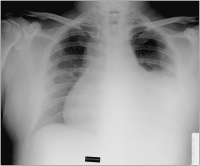

Thoraxröntgen

Abbildung 2: Thoraxröntgen vor Drainage

Kardiologie

Röntgenbild

Thorax